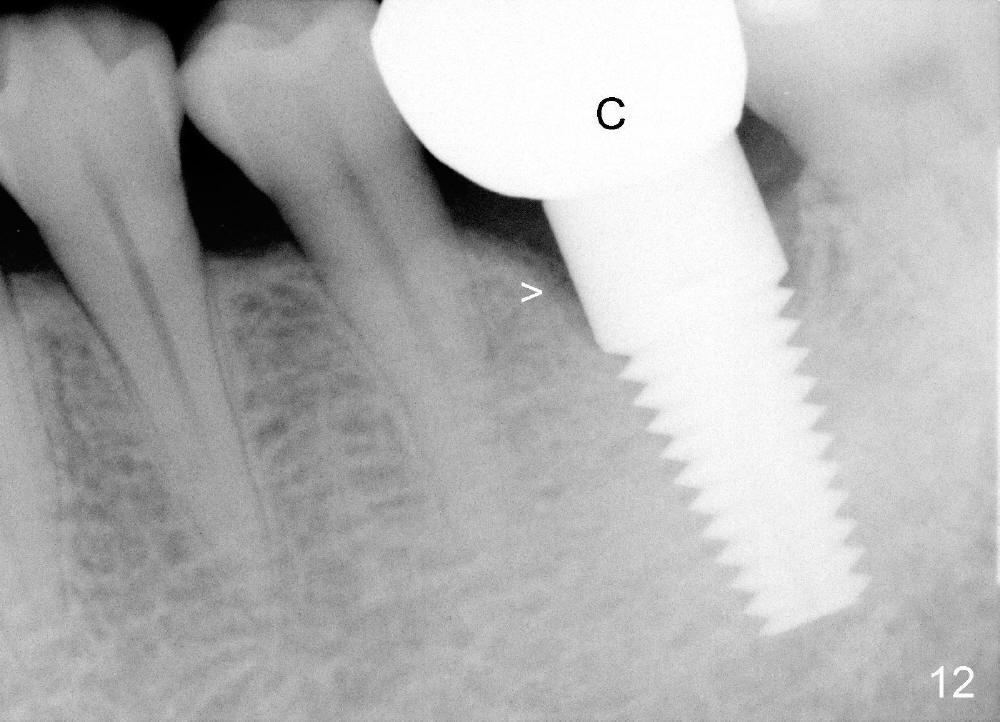

Two and a half months post cementation, the buccal metal show is much less and confined to the midbuccal portion. It appears that the papillae increase their mesiodistal dimension (data not shown). Bone appears to remain stable over the implant surface 2.5 and 9 months post cementation (Fig.12 >,13). The papillae around the implant crown remain normal 11 months post cementation (Fig.14 *). No bone loss is noticed 26 (Fig.15) or 38 (Fig.16) months post cementation. There is no bone loss around the 7x17 mm tissue-level implant 6 years 8 months post cementation (Fig.17).